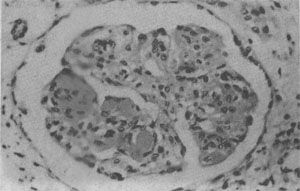

狼疮性肾小球肾炎

图4-10 狼疮性肾小球肾炎

肾小球毛细血管丛节段性纤维素样坏死,伴系膜细胞增生;间质炎细胞浸润

(1)肾:肾功能衰竭是SLE的主要死亡原因。SLE病人几乎均有不同程度的肾损害,约60%病便以狼疮性肾炎为主要表现.常见的类型有系膜增生型(10%~15%)、局灶增生型(10%~15%)、弥漫增生型(40%~50%)和膜型(10%~20%)。各型狼疮性肾炎的病变,类同于相应的原发性肾小球肾炎,各型病变间常有交叉,因此肾小球的病变呈多样性,晚期可出现典型的硬化性肾炎的表现。肾炎病变的发生主要基于肾小球中免疫复合物的沉积,可位于系膜区、内皮下和上皮下。其中弥漫增生型狼疮性肾炎中内皮下大量免疫复合物的沉积,是SLE急性期的特征性病变。在弥漫增生型及膜型病例中,约半数病例在间质及肾小管基膜上亦有免疫复合物沉积,因此肾小球病变和间质的炎症反应在狼疮性肾炎中十分明显(图4-10)。苏木素小体的出现有明确的诊断意义。